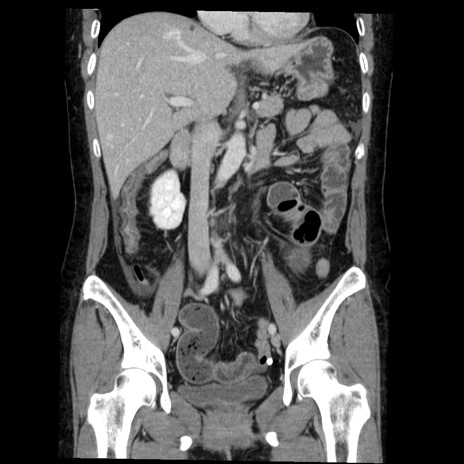

矢状断像

症例6(冠状断像)

【症例】50歳代女性

【主訴】下腹部痛

【現病歴】本日朝より下痢2回あり。 昼食を食べた後、嘔吐3回、下腹部痛認め、症状軽快せず、当院救急搬送。

最終食事:本日昼(生ものなし)。 昨日の夜、刺身を食ぺたとのこと。周囲に同様の症状の者なし。普段、排便は毎日あるとのこと。

【既往歴】卵巣癌術後(8年前に当院で卵巣摘出)

【身体所見】 意識清明、腹部:平坦、腸蠕動音→、やや硬、下腹部自発痛・圧痛あり、反跳痛あり、筋性防御なし。

【データ】WBC 16000、CRP 0.01